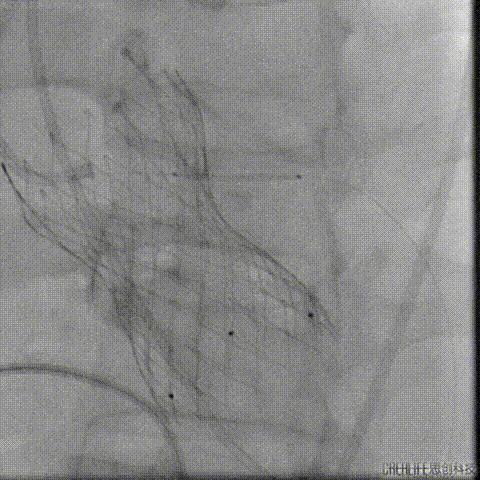

TAVR术后3日Hb较前下降 (63g/L)

CT提示左侧腹膜后、髂窝及腹股沟区巨大血肿

行急诊手术 腹主动脉及左侧股动脉造影

左侧股动脉见造影剂外渗

球囊压迫后植入覆膜支架

复查造影